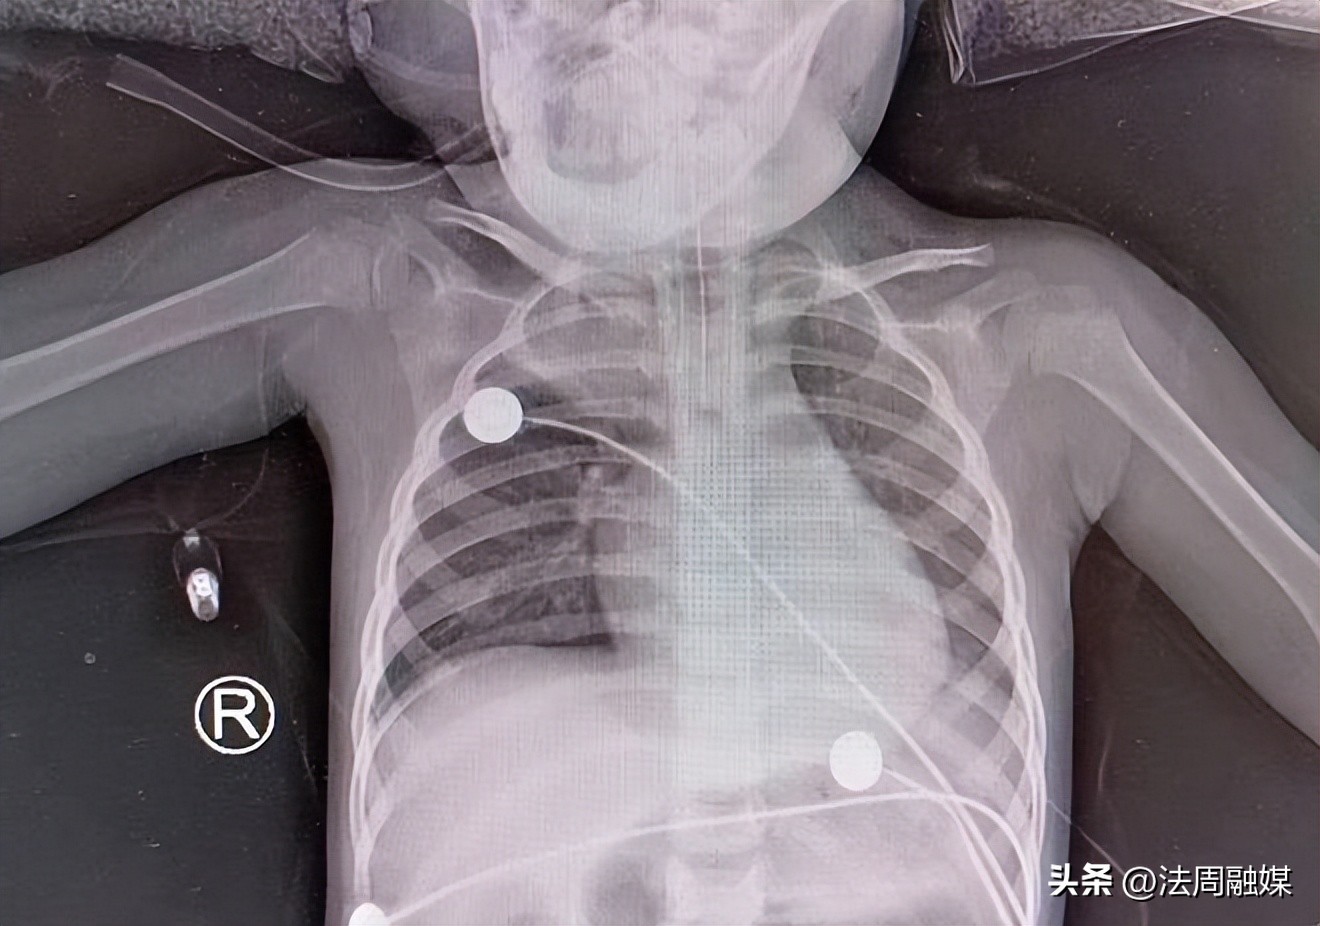

支气管异物被取出,患儿气道变通畅

术后,患儿肺部功能恢复正常